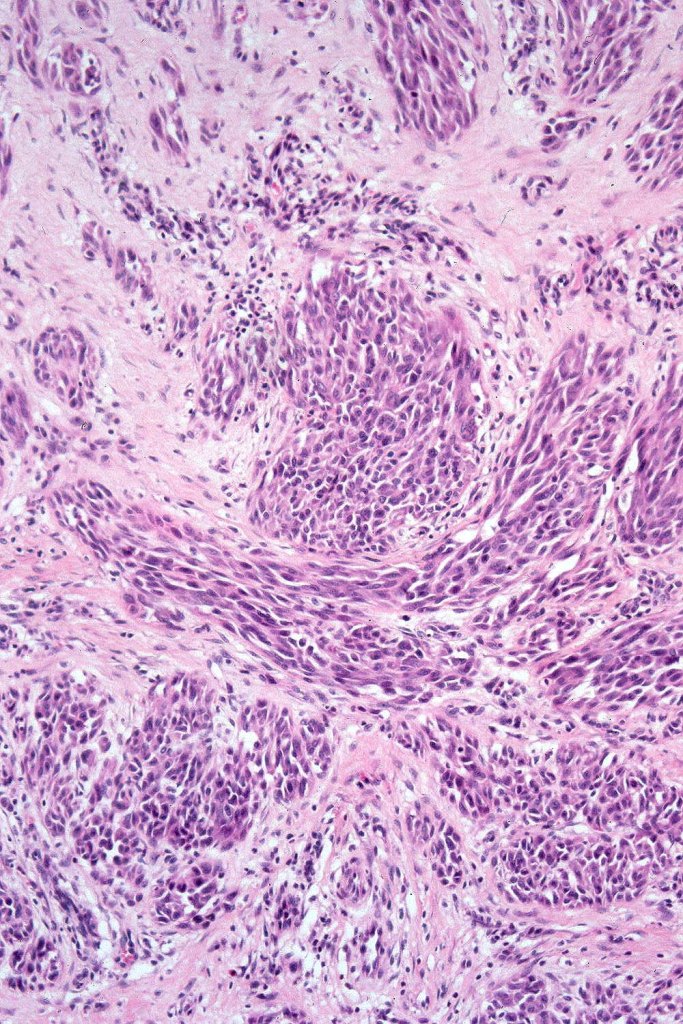

•Junctional nests often vertically orientated, dyscohesive with a surrounding retraction artifact

•Pleomorphism is almost invariable but affects all of the population to the same extent i.e., the cells & nuclei all look very much the same

•Kamino bodies (often multiple) are a characteristic feature